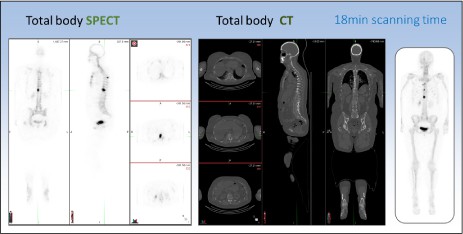

Tranziția către imagistica 3D de rutină cu tehnologia SPECT de nouă generație

Detectorii digitali care captează un număr maxim de fotoni oferă imagini 3D detaliate, superioare tehnologiei planare Anger. Sistemul SPECT/CT multifuncțional permite scanări complete cap–picioare într-o singură sesiune, oferind informații precise și reducând disconfortul pacientului.

- Workflow-ul SPECT/CT total-body cu acoperire continuă de 2 m oferă eficiență superioară și informații detaliate față de scanările planare tradiționale. Imaginile 3D corectate pentru dispersie, atenuare și volum parțial pot genera, la nevoie, vizualizări multi-view planare (MVP).

- Îmbunătățirea detecției leziunilor este doar începutul. O singură scanare completă oferă imagini 3D de tip PET, reducând timpul de examinare și permițând utilizarea unei doze mai mici, optimizând modul de desfășurare al investigațiilor imagistice.